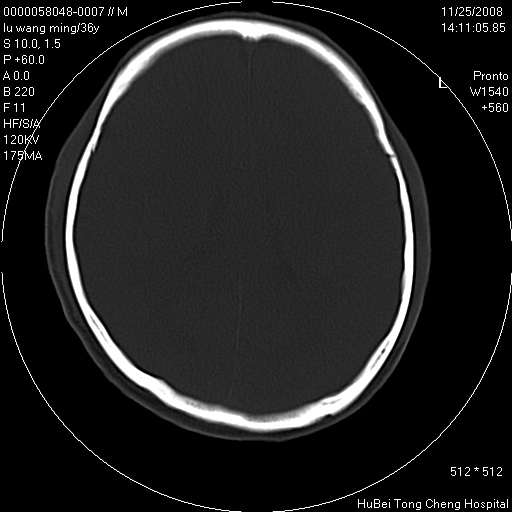

患者 男,36岁。头部烧伤36年伴溃烂,经久不愈。患者几个月大时,倒入火炉不幸烧伤头部,后长期溃烂,经久不愈。

临床诊断:1)头皮烧伤并感染。2)颅骨病损?

颅脑ct轴位平扫(层厚、层距均匀10mm),图像如下: